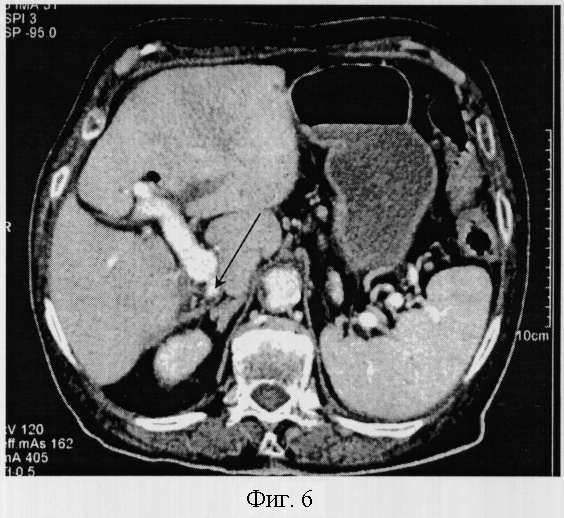

Пример 6. Аплазия правой доли.

Больная Кибицская А.М. 86 лет обследовалась по поводу острого живота. При проведении компьютерно-томографического исследования обращает на себя внимание декстрапетальное расположение печени. Форма печени овальная, края закруглены. Общий объем печени составлял 1216,4 см3 и полностью относился к левой доле. Объем сегментов левой доли, за исключением первого, значительно увеличен и составил 14,2; 327,3; 494,1; 380,8 см3, соответственно номеру сегмента. Паренхима правой доли печени отсутствует. При венозной фазе контрастирования отчетливо определяется культя правой ветви воротной вены.

Отсутствие правой ветви воротной вены и паренхимы правой доли печени позволило диагностировать аплазию правой доли печени и гиперплазию сегментов левой доли печени (фиг.6).